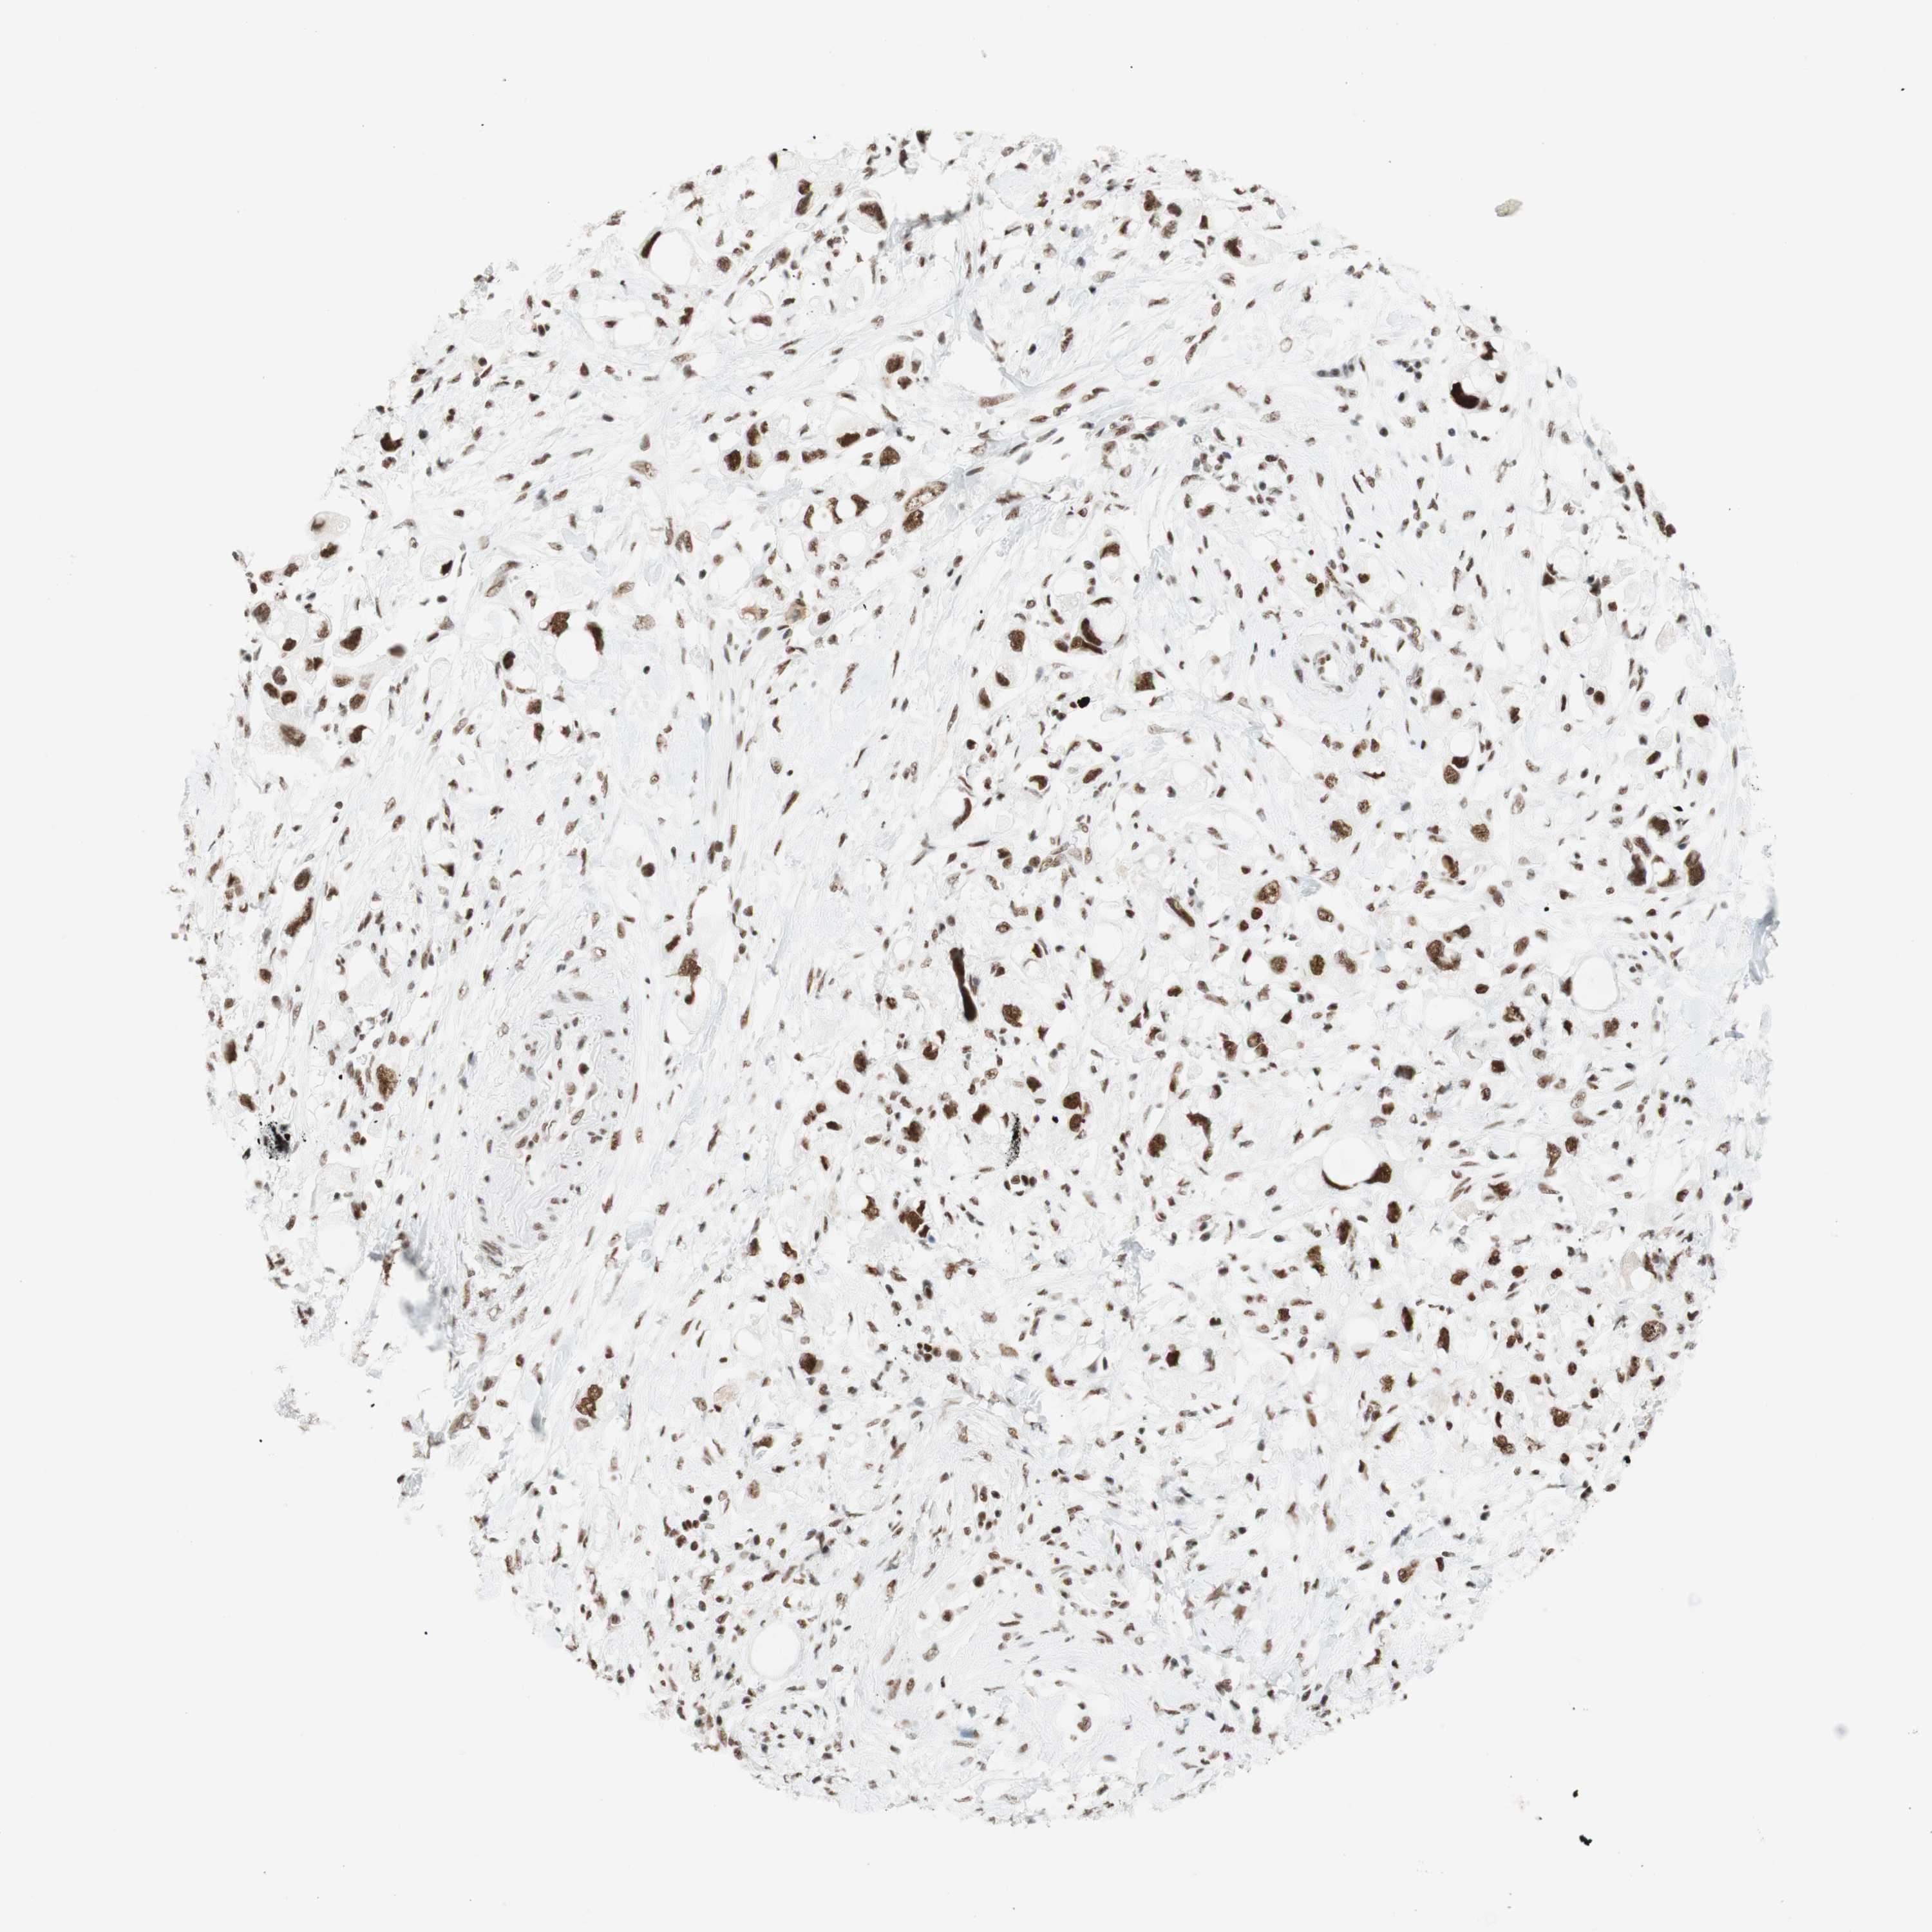

PANCREATIC CANCER - Protein expressioni

A mouse-over function shows sample information and annotation data. Click on an image to view it in a full screen mode. Samples can be filtered based on level of antibody staining by selecting one or several of the following categories: high, medium, low and not detected. The assay and annotation is described here.

Note that samples used for immunohistochemistry by the Human Protein Atlas do not correspond to samples in the TCGA dataset.

Antibody stainingi

Antibody staining in the annotated cell types in the current human tissue is reported as not detected, low, medium, or high, based on conventional immunohistochemistry profiling in selected tissues. This score is based on the combination of the staining intensity and fraction of stained cells.

Each image is clickable and will lead to virtual microscopy that enables deeper exploration of all samples and also displays staining intensity scores, fraction scores and subcellular localization as well as patient and tissue information for each sample.

Antibody CAB012478

Staining

High

Medium

Low

Not detected

Intensity

Strong

Moderate

Weak

Negative

Quantity

>75%

75%-25%

<25%

None

Location

Nuclear

Cytoplasmic/membranous

Cytoplasmic/membranous,nuclear

Adenocarcinoma, NOS

Adenocarcinoma, metastatic, NOS